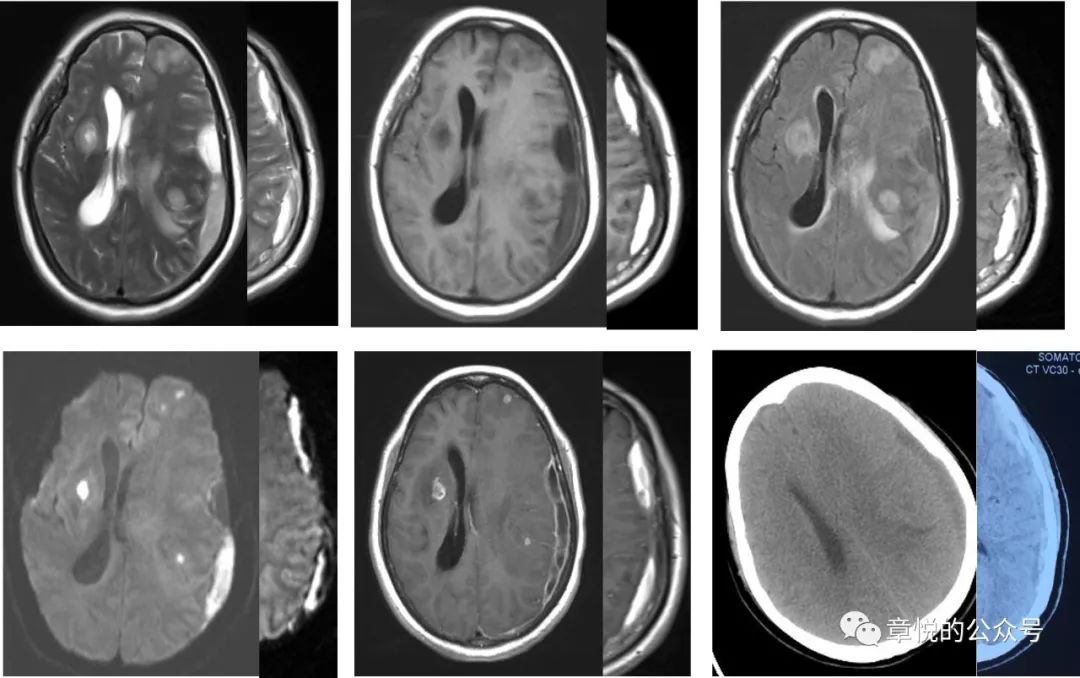

硬膜下脓肿在DWI上信号也很高,这与硬膜下血肿很相似,不过在其他序列上两者有显著差别,近来正好有一例硬膜下脓肿,可以对比一下(图4)。硬膜下脓肿是严重的颅内感染,有高热,大汗淋漓、头痛、血白细胞计数、血沉、C反应蛋白升高等表现,而这些是患者没有的。

图4 硬膜下脓肿和血肿对比,左侧大图为脓肿,右侧半幅小图为血肿,两者T2和DWI比较相似,而T1和FLAIR相差别较大

病人入院后癫痫频发,那会不会是癫痫后的表现呢?癫痫持续状态后出现磁共振异常表现的概率为11.6%,主要的改变有海马受累,胼胝体压部受累,皮层加丘脑受累,皮层受累和小脑交叉性失联络等(图8),影像改变能持续多长时间没有大宗报道,从小样本的研究看,部分病例在发病2周时仍旧有信号改变,这一点我们的案例倒是符合的。

图8 癫痫后脑磁共振异常的形态,海马受累,胼胝体压部受累,皮层加丘脑受累,皮层受累和小脑交叉性失联络等。(Milligan TA. et alFrequency and patterns of MRI abnormalities due to status epilepticus. Seizure- European Journal of Epilepsy , Volume 18 , Issue 2 , 104 – 108)

患者入院后,我们发现他的血糖十分高,空腹血糖11 mmol/L,餐后高达18 mmol/L,糖化血红蛋白超过11%,起初家属对我们提出的胰岛素治疗有点感冒,但连续3天患者情况不好于是就听从我们的意见,晚上一针下去,第二天早上血糖降到7 mmol/L,患者意识障碍明显好转,并且能够连词成句了,家属对此十万分的满意,毕竟是华山医院,一针见效!此后的几天,病人空腹血糖基本就控制6-7 mmol/L,餐后血糖8-9 mmol/L,病人情况一天好过一天,到第5天,家属感觉病人情况已经好了8-9成,查体患者对答切题,言语流利,计算力正常,虽然有时候找词有点困难,但已经不妨碍他正常表达了,接着DSA检查排除了血管畸形,复查头颅磁共振发现脑叶肿胀和异常信号消失。当出院时询问患者入院时的情况,他丝毫没有印象(图9)

图9 经过降糖治疗,脑叶肿胀和异常信号消失